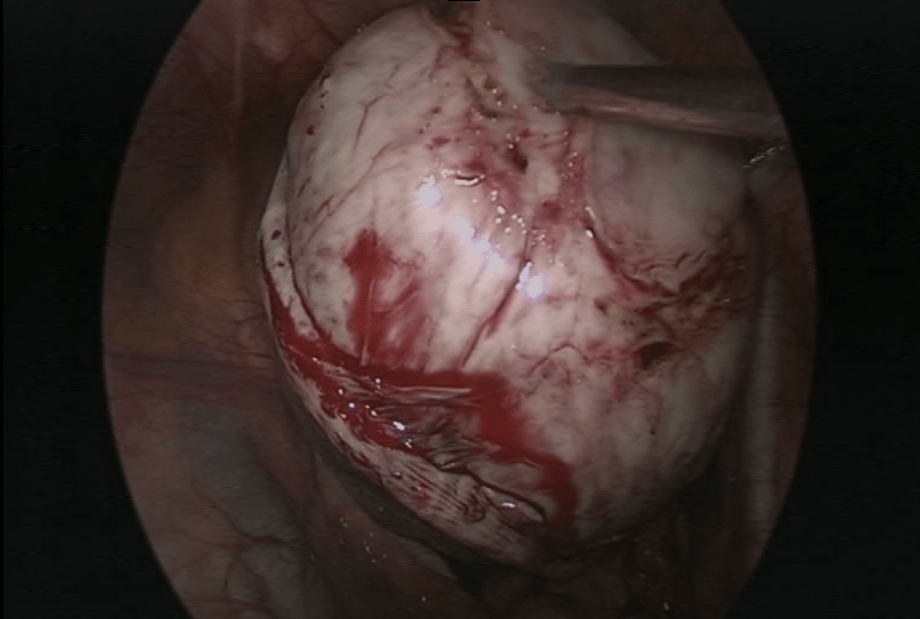

Not all fibroids require treatment, but problematic, large, or growing fibroids need medical intervention. Laparoscopy is a minimally invasive surgical approach that offers an effective solution for fibroid removal. This technique allows for the removal of even large and multiple fibroids with minimal discomfort and quicker recovery times.

High-definition cameras and instruments ensure accurate removal.

Depending on the patient’s age and desire to have children, laparoscopic surgery can involve the removal of just the fibroids or, in some cases, the uterus. Each treatment plan is tailored to the individual needs of the patient.